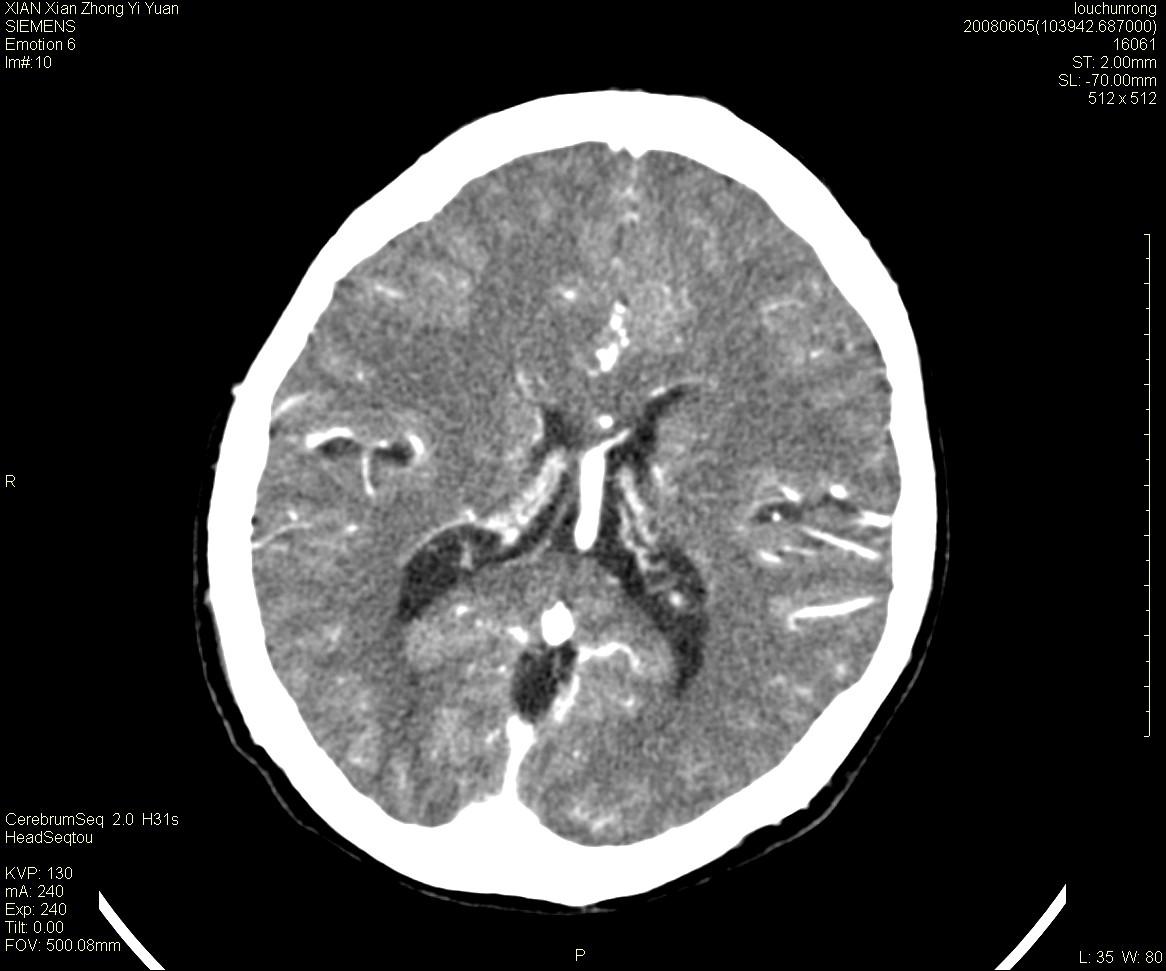

标题: CT13860:F52Y,,头外伤致头晕半天,以前无不适。 [打印本页]

标题: CT13860:F52Y,,头外伤致头晕半天,以前无不适。

层厚2mm。

左侧侧室内血管异常增粗,考虑血管变异或血管瘤可能,余未见异常

静脉窦血栓? mri检查

大家看左额叶大脑镰旁高密度影

两侧脑室体部距离增宽,胼胝体发育不良?

中线附近、枕叶近枕骨处及脑内多发点条状强化影,考虑血管异常?

大脑大静脉池内的密度不均,双侧脑室增宽,我看右异常这块。战友们看看